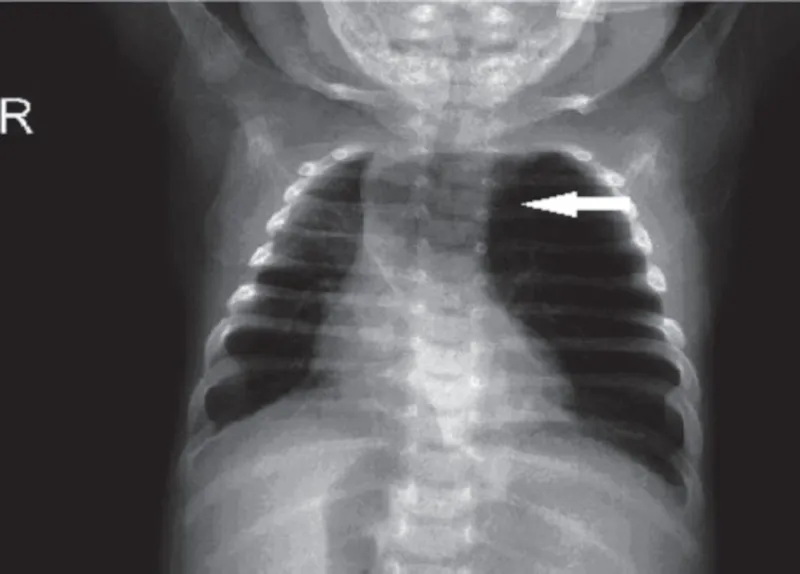

- Diagnosis: Prenatal USG; postnatal CXR (cysts, shift), CT definitive.

- Dx: CXR (hyperlucency, mediastinal shift).

- Dx: CXR (round opacity); CT.

- Prenatal ultrasound often detects; CT scan confirms and details postnatally.